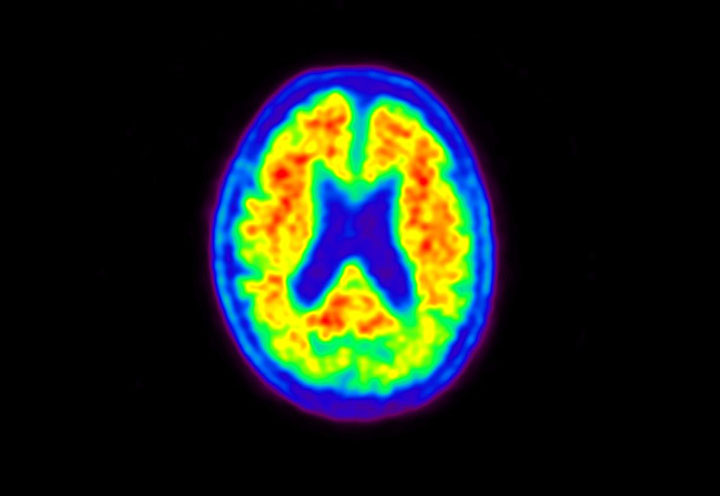

Head / Case5 : Amyloid

Axial

Courtesy : Kindai University Hospital

- Imaging protocol

- Injected dose: 4.27 MBq/kg, 18F-Flutemetamol

- Uptake time: 99 minutes

- Scan time: 20 minutes